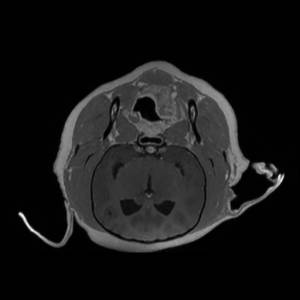

Main Gallery

Playing with a photo gallery function. It is possible to have multiple galleries, each within a namespace.